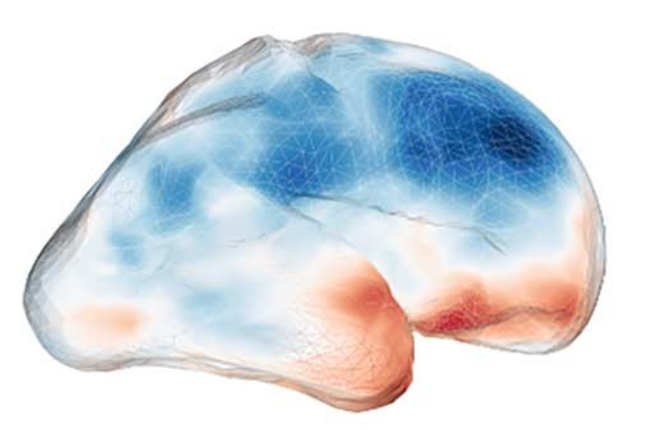

Neuroimaging

We are mapping the functional organisation of the human brain based on functional magnetic resonance imaging (fMRI) in healthy as well as diseased adults.